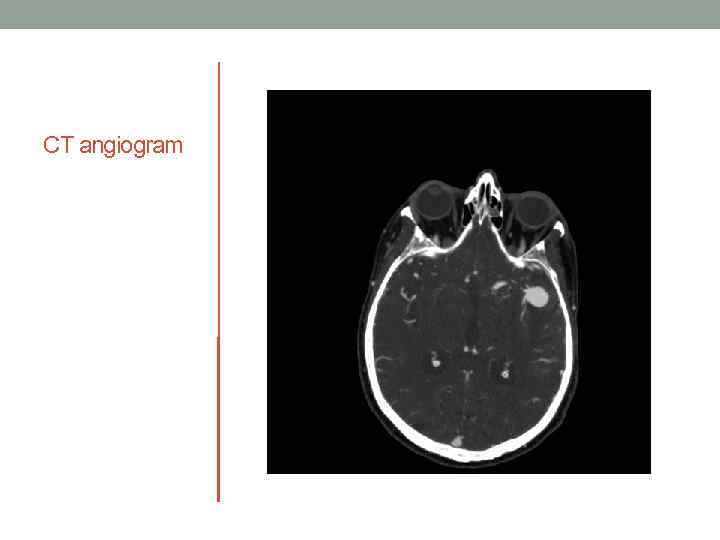

CT angiogram